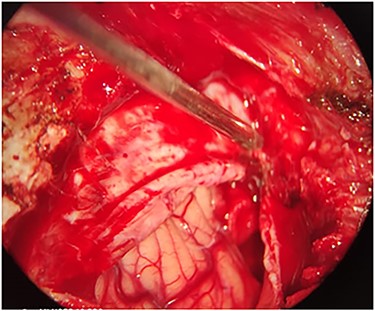

The patient underwent a left unilateral retrosegmoid craniectomy in the park bench position. However, although the contused brain tissue was drained (Fig. 2), the projectile was not found in the suspected point.

Intra-operation image shows the contused brain tissue which was caused by bullet in left cerebellar hemisphere.